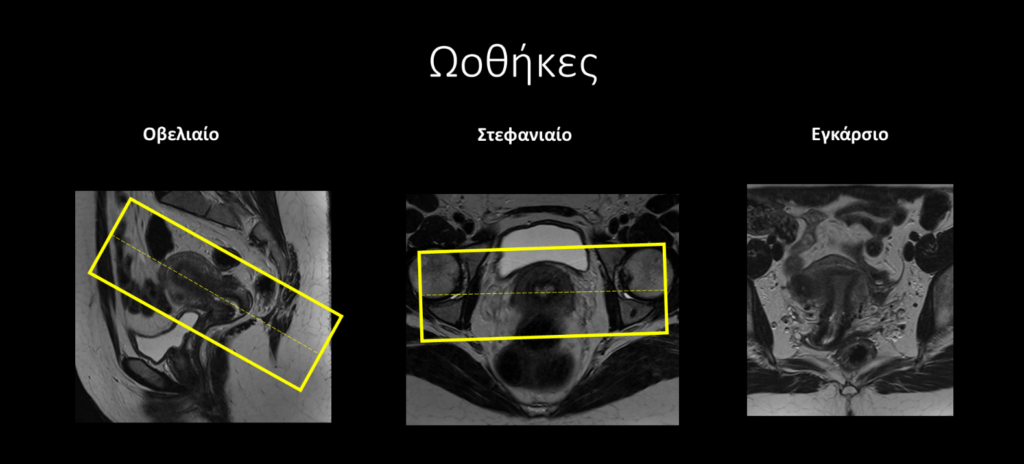

3. Ωοθήκες: στην λοξή εγκάρσια ακολουθία δίνεται παράλληλη κλίση με την μήτρα, ενώ στην λοξή στεφανιαία δίνεται κάθετη κλίση στη μήτρα.